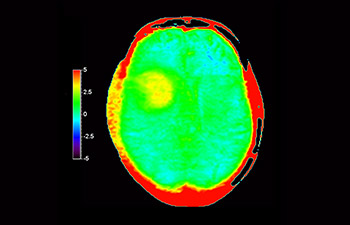

3D APT (Amide Proton Transfer, transferencia de protones de amidas) es un exclusivo método de adquisición de imágenes por RM cerebral sin contraste que tiene por objetivo ofrecer un diagnóstico de neurooncología más fiable. 3D APT utiliza la presencia de proteínas celulares endógenas para producir una señal de RM que se corresponde directamente con la proliferación celular, que es un marcador de la actividad tumoral. 3D APT puede ayudar a los profesionales de la salud debidamente instruidos a diferenciar los gliomas de baja malignidad de los gliomas más graves, así como a diferenciar la progresión tumoral del efecto del tratamiento1.

Cerebro con glioblastoma

con 3D APT